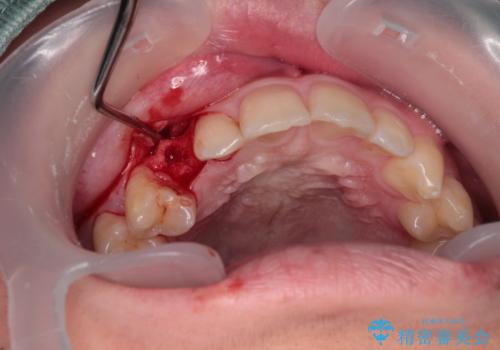

- 永久歯が生えてこず、欠損になっていることを気にして来院された患者様です。

CT撮影を行ったところ、埋もれている犬歯を牽引して萌出させることは不可能と判断し、インプラントによる補綴治療を行うこととしました。

現在では、埋入時に仮歯を装着する「即時荷重インプラント」での取り扱いとなりますが、治療当時は未導入であったため、従来の複数回の外科処置を行う術式で治療を行いました。